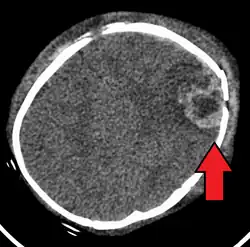

| An intraparenchymal bleed with overlying skull fracture from shaken baby syndrome | |